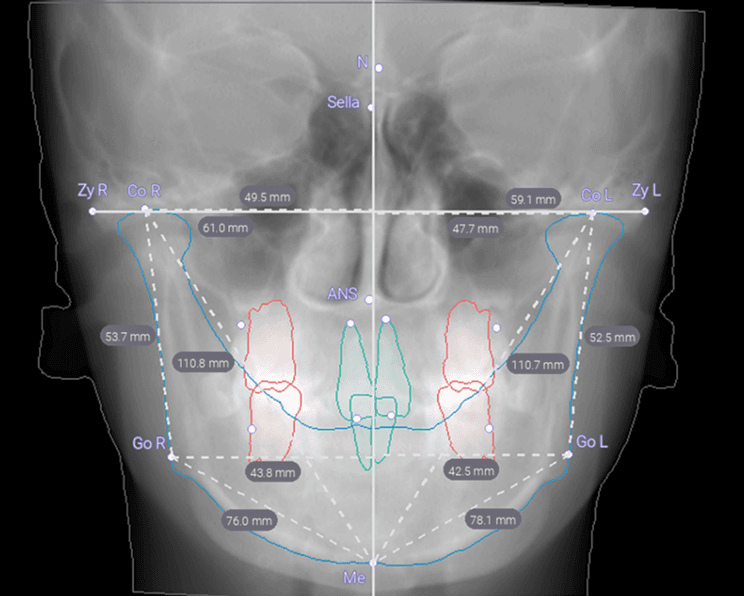

Take Your 3D Experience to the Next Level

With automatic segmentation, CBCT scans are converted into 3D STL models.